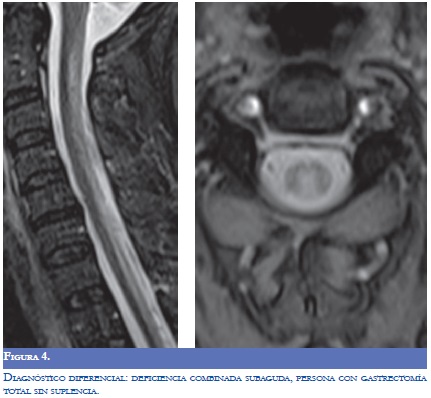

Una consideración importante en la aproximación diagnóstica consiste en descartar que el síndrome clínico sospechado no se relacione con disfunción orgánica múltiple asociada con patologías agudas, por procesos infecciosos, con efectos secundarios de medicamentos, anormalidades metabólicas como la uremia y otras (Figura 4) (8). Otras entidades para tener presente son: la leucoencefalopatía multifocal progresiva, la tuberculosis, la sífilis, la demielinizacion por virus como el VIH, el virus de sarampión asociado con la Pan Encefalitis Esclerosante Subaguda (PEESA) (4). La infección óptica. por el virus Linfotrópico de célula T humana tipo l (HTLV I) se asocia con una mielopatia inflamatoria crónica que clínicamente se manifiesta como una mielitis transversa. La infiltración linfocítica perivascular es el marcador histológico, se infectan los linfocitos CD4 que pueden detectarse en el sistema nervioso. La evolución crónica y la progresión lenta dificultan el diagnóstico diferencial con la EM y otras causas de mielopatía; se reporta que la medición simultánea de la carga viral de HTLVI en el LCR y en células mononucleares de sangre periférica ayuda a depurar el diagnóstico, el incremento en la relación con manifestaciones clínicas agudas orienta hacia esta entidad viral (10).